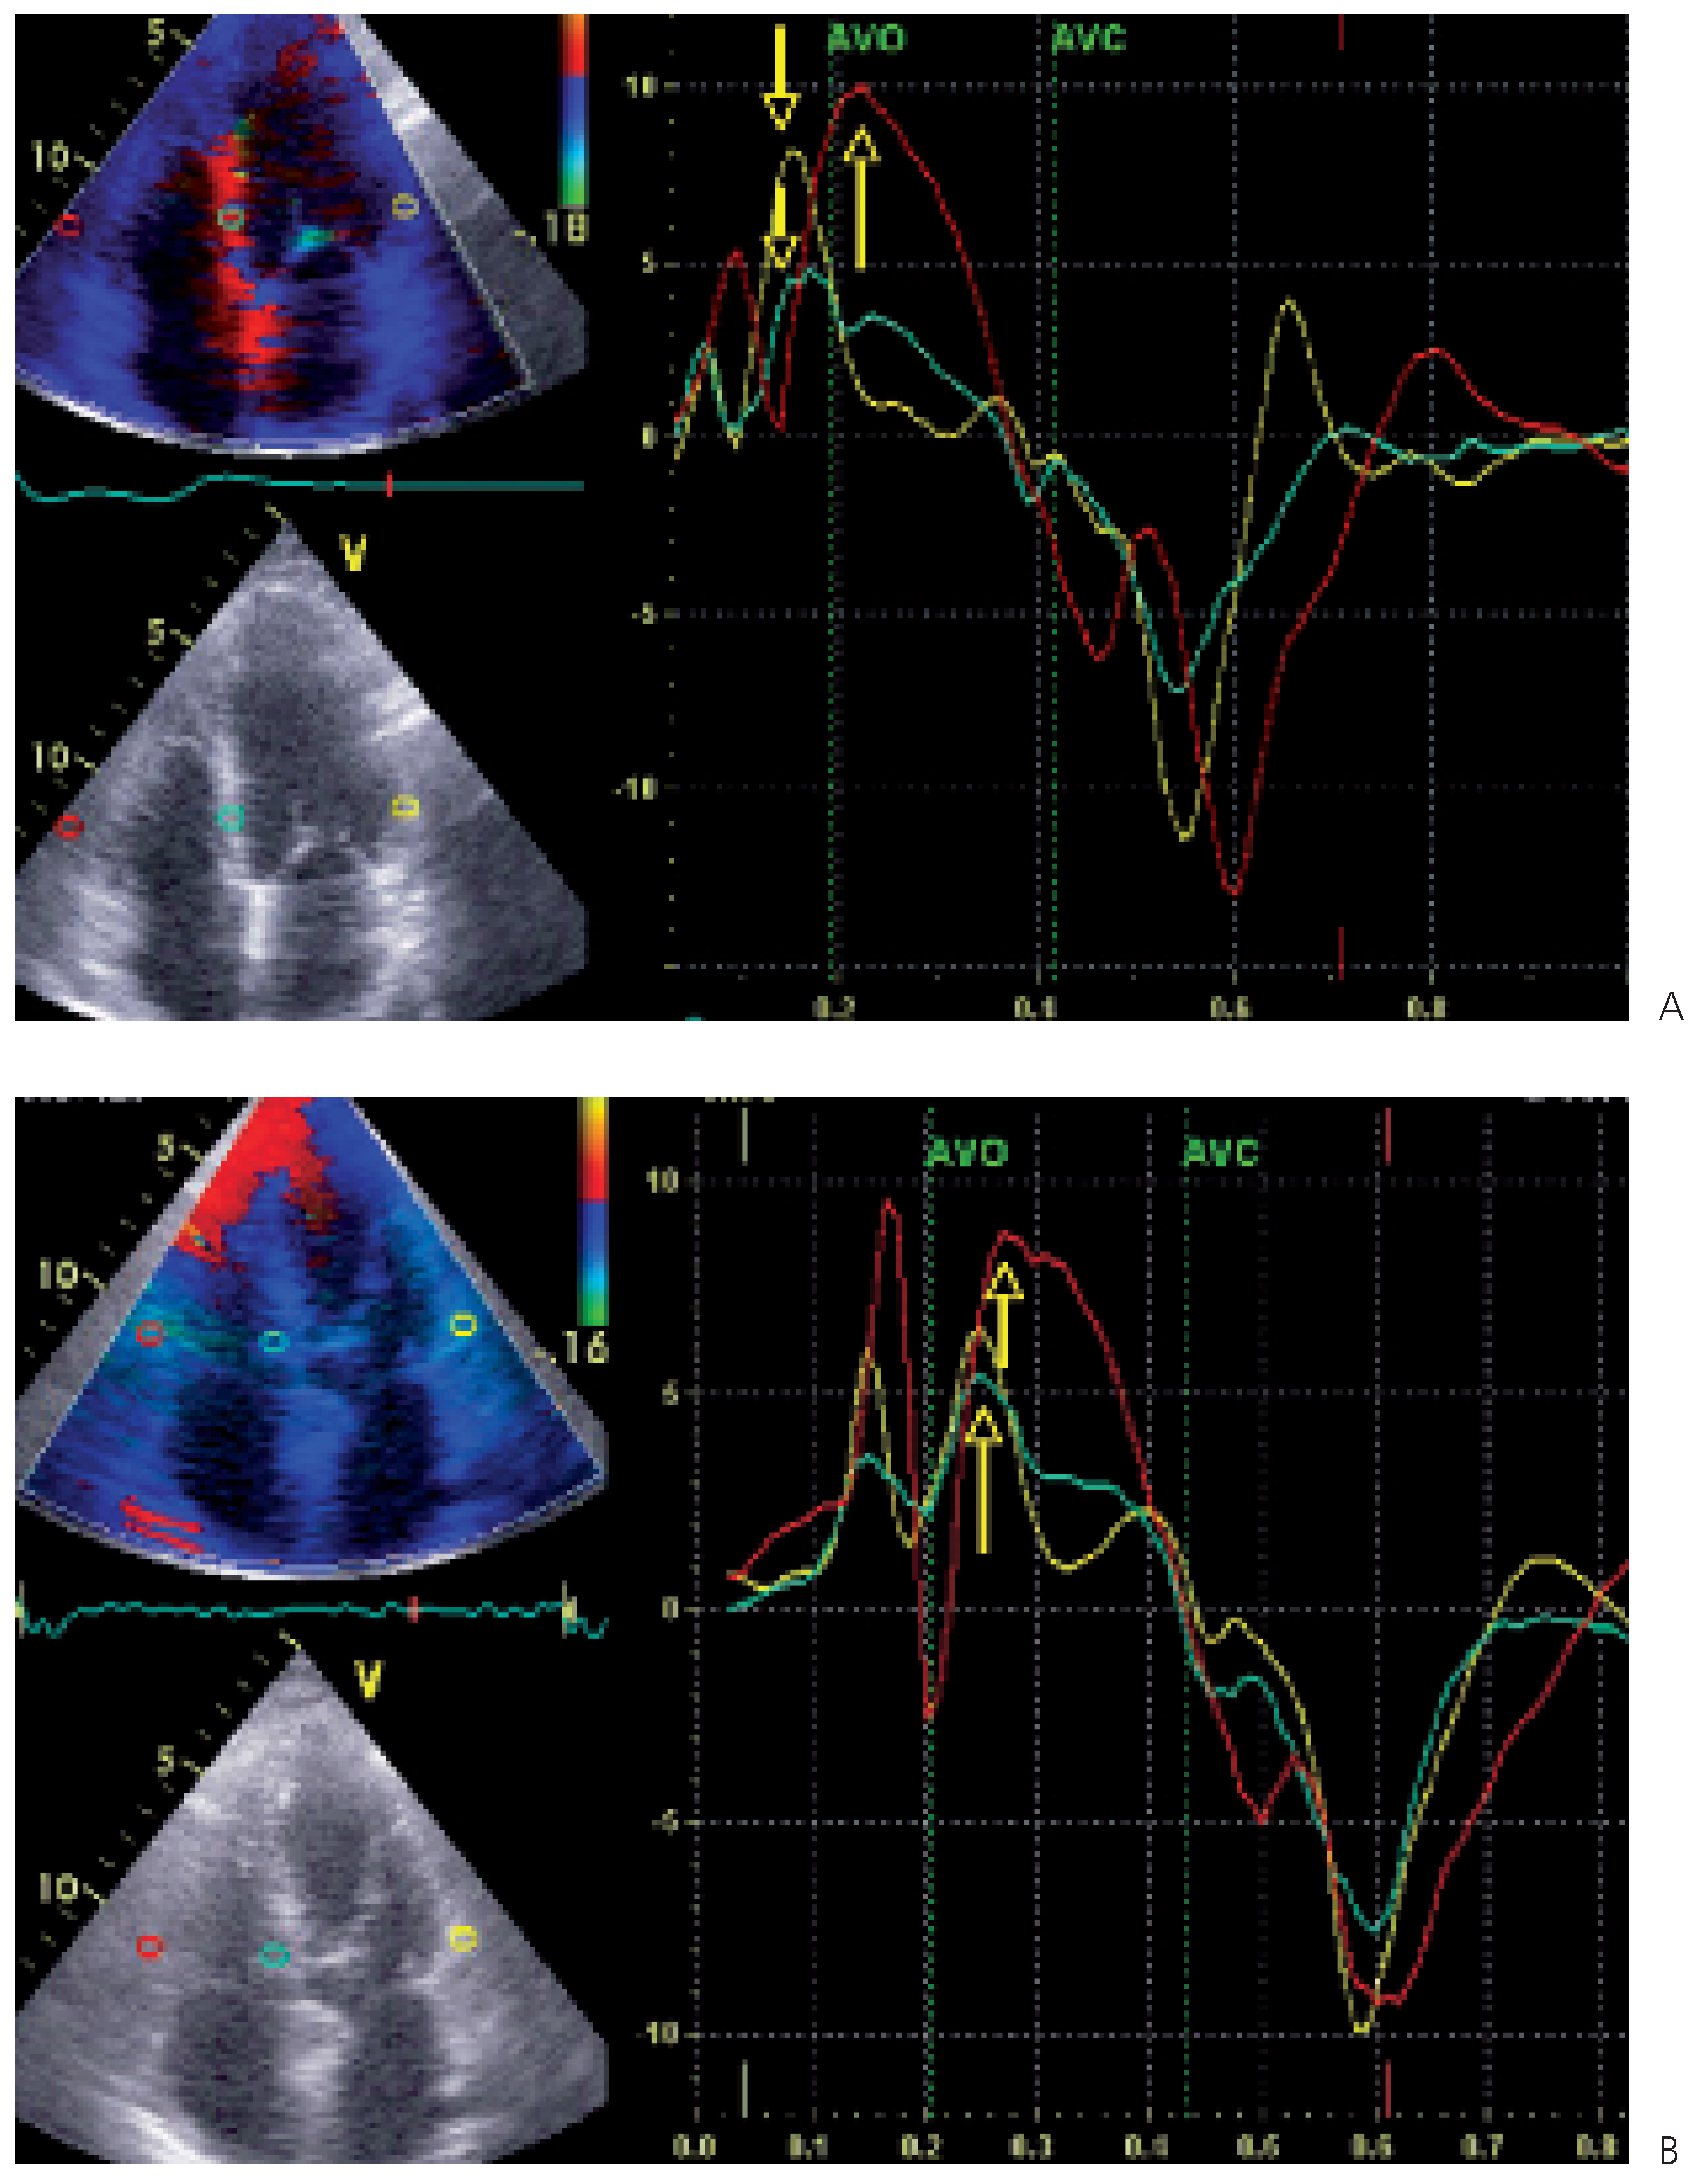

- Optimalisation du délai interventriculaire